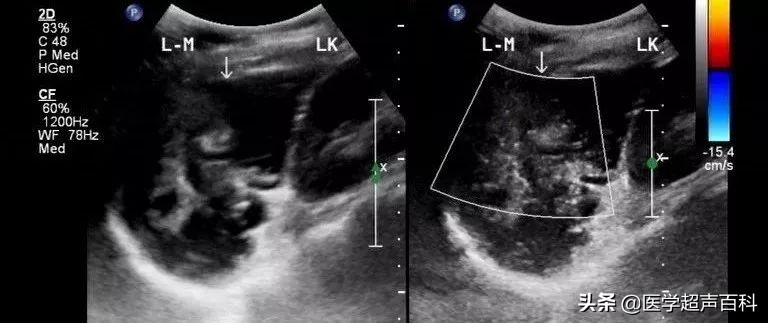

超声表现为右下腹与盲肠相连的类圆形或管状无回声包块,其横径通常大于1.5cm,包块边界清楚,壁厚,内壁不光整,内部可呈无回声或条带状高回声分隔混杂的不均质表现(可误认为是囊实混合性包块),也有病例报道较大的肿瘤可呈“洋葱皮”样,CDFI:部分肿瘤囊壁内可见少量血流信号。